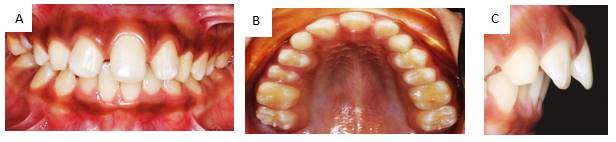

Descripción del caso clínico

Paciente masculino de 10 años de edad, peso 23 Kg., estatura 123 cm., procedente de Jamundí, Valle del Cauca- Colombia. Asiste a consulta, en compañía de su tía, responsable del menor, quien refiere como motivo de consulta: “Mi sobrino tiene un solo diente adelante”. Al interrogatorio refiere: El niño es el segundo hijo de tres embarazos llevados a término; Antecedentes familiares, tía paterna padece diabetes, hipertensión y cáncer sin especificar. Antecedentes personales no reporta; la tía refiere que el niño, en la dentición decidua también presentó un solo incisivo central superior. Además, relata que sus otros dos hermanos presentan el mismo problema. Al examen extraoral se observa que la línea media no coincide con la punta de la nariz, ni con el centro del mentón; no presenta filtrum labial, el plano bipupilar no es paralelo a la línea comisural; existe incompetencia labial; orejas de tamaño, proyección e implantación aumentadas. (Figura 1) En el examen intraoral se observa un incisivo central único sobre la línea media del maxilar, ausencia de frenillo labial y papila incisiva, paladar oval y maloclusión clase II con proinclinación de incisivo central. (Figura 2 a, b y c).

Se realizan estudios complementarios: modelos de estudio, radiografías panorámica y lateral de cráneo, fotos extra e intraorales, para realizar un correcto diagnóstico e el iniciar tratamiento.